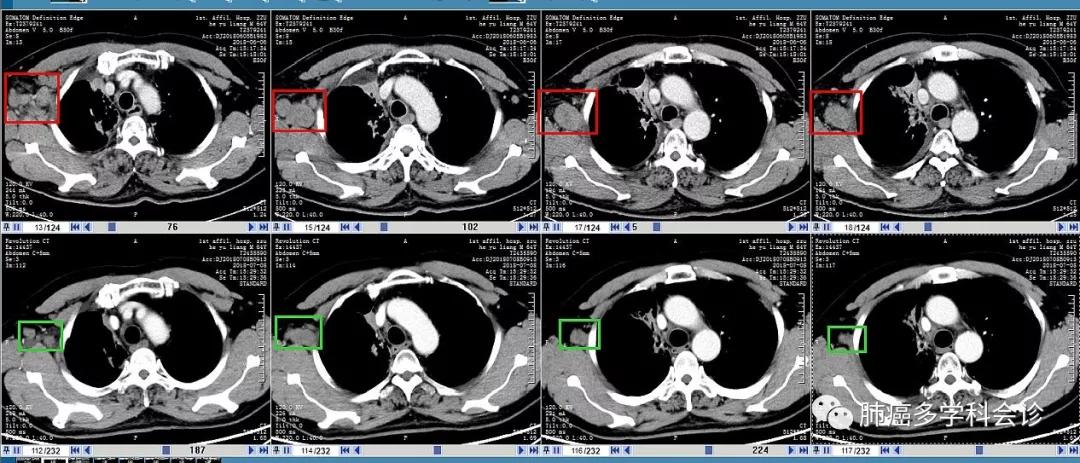

以下是2周期治疗前(每图上行,2018-06-06)和治疗后(每图下行,07-08)腋窝和纵隔转移淋巴结大小等的比较: